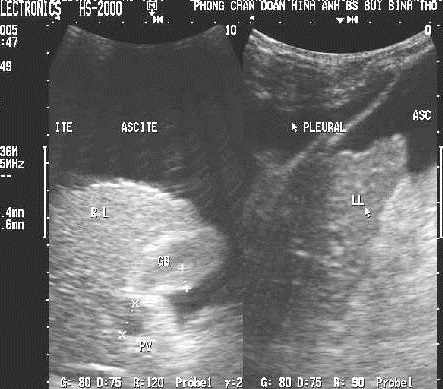

Images echographiques de cirrhose du foie au stade

avance avec ascite de large volume : La volume du foie est diminue ,

hyperechorich echogene avec sa bordure tres irregulie . Une

ascite a grand

volume et pleuresie pleurale gauche . Veine porte dilate important avec diametre

surpasse 12,5 mm ( normalement < 11mm ) . |